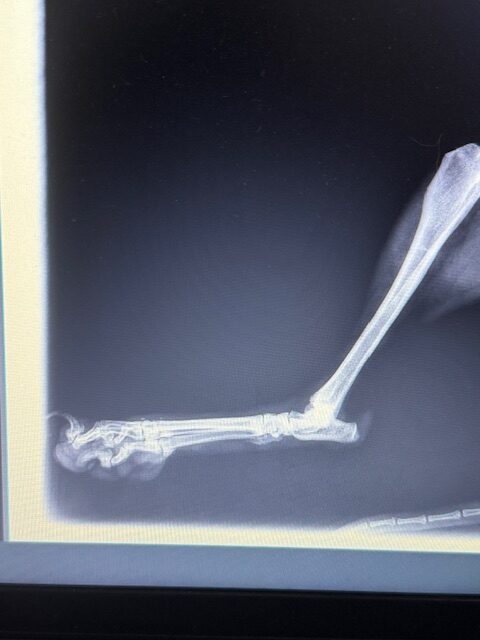

Peaches was rescued from Ramlet el Bayda. She was shot by an official from the municipality. Her leg was completely shattered. We had to amputate! She’s very mellow, sweet and is good with other dogs. DOB: 8/8/2017